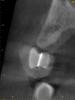

kriokov Опубликовано 16 октября, 2012 Поделиться Опубликовано 16 октября, 2012 Sahan, а можно фото шаблона изготовленного таким способом?способ простой. которым пользуемся1.модель с моделировкой,2.потом через восковую моделировку вставляется проволока,3.сверху силикон базисный, проволока приливается паттерн резином4. каппа из базиса снимается с модели, из модели убираем восковые зубы, внутрь шаблона заливаем пластмассу - Structur, она рентгеноконтрастна5. Все это помещаем на модель до отвердивания пластмассы6. Спиливаем рога и паттерн-резин7. шаблон доводим , чтоб в рот посадить8. кросс-секции с шаблоном 3 Ссылка на комментарий